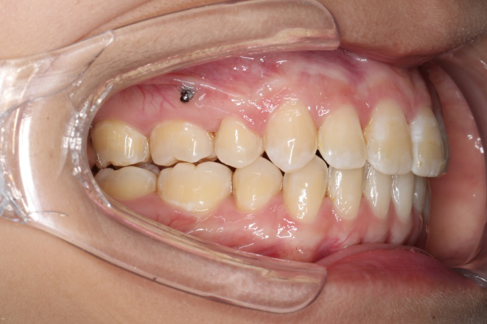

• 磨牙,尖牙I类关系,中线齐

• 上下牙列中度拥挤

• 上下前牙唇倾

IntraoralExamination(2016-08.31,Wu)

2018.11.14  术后磨牙尖牙I类关系,中线齐,覆合,覆盖正常

Post-TXPRE-TXPost-TXNormFMIA°47°57.555.0SNA°77.7°76.883.0SNB°70.2°73.780.0ANB°7.5°3.13.0FMA° 29.828.026PFH/AFH70.5°65.970Z Angle°50.3°64.477U1-FH113.0103.7110.0 IMPA°103.291.197.0U Lip tos’ line6.3 mm3.25.0L Lip to s’ line3.9 mm1.03.0OP-FH1212.615